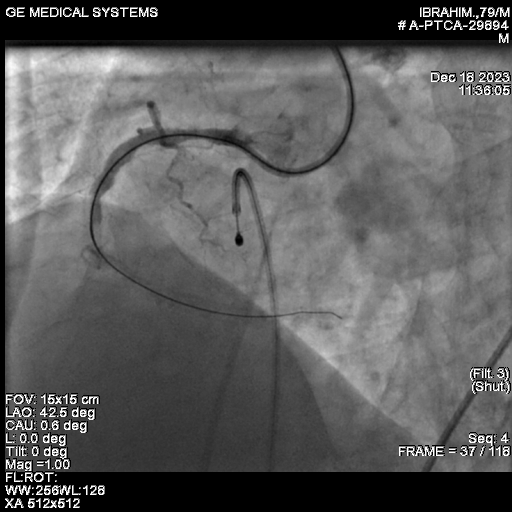

We proceeded with Percutaneous Transluminal Coronary Angioplasty (PTCA) of the Right Coronary Artery (RCA), utilizing ROTAPRO SUPPORT due to the calcified nature of the lesion. The CTO was successfully crossed using a Conquest Pro wire. Intravascular imaging, specifically Optical Coherence Tomography (OCT), confirmed the presence of multiple calcified nodules, highlighting the difficulty of the case.A 1.5 Rotapro was used for preparation.

After adequate lesion preparation, we deployed a 4x 38 mm DES. The post-PCI angiogram confirmed a successful final result in the RCA.Following the successful procedure, the patient was shifted to the CCU. Unfortunately, he rapidly developed hypotension and sweating. An urgent ECHO was performed, which revealed a massive pericardial effusion (PE).We maintained continuous pericardial aspiration. The patient's ACT was 280, and Protamine was administered to reverse the heparin effect. A check angiogram ruled out any wire-induced perforation, suggesting the perforation was likely iatrogenic from the temporary pacing wire that had been placed for Rotapro support. Pericardial aspiration continued, and CTS opinion was sought, with the high risk of surgical intervention being explained to the family.At this critical juncture, given the refractory nature of the bleeding, we looked to a new strategy. Literature supports the use of intra-pericardial thrombin injection as a bailout strategy for iatrogenic pericardial tamponade. The response to the intra-pericardial thrombin injection was prompt. The patient's hemodynamics gradually improved. He had an uncomplicated recovery and was discharged five days later.